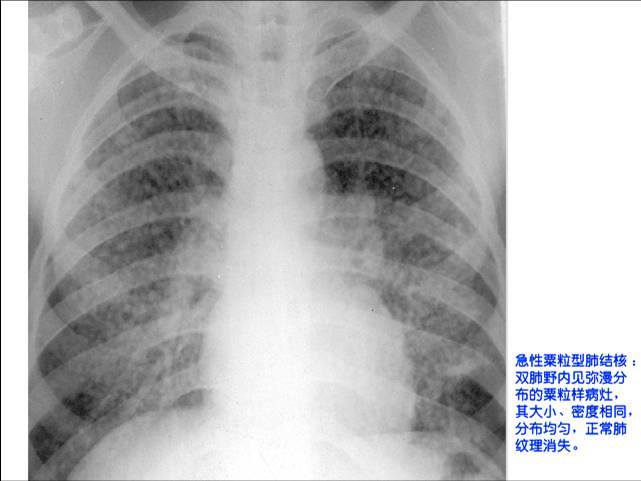

照片名称:急性粟粒型肺结核